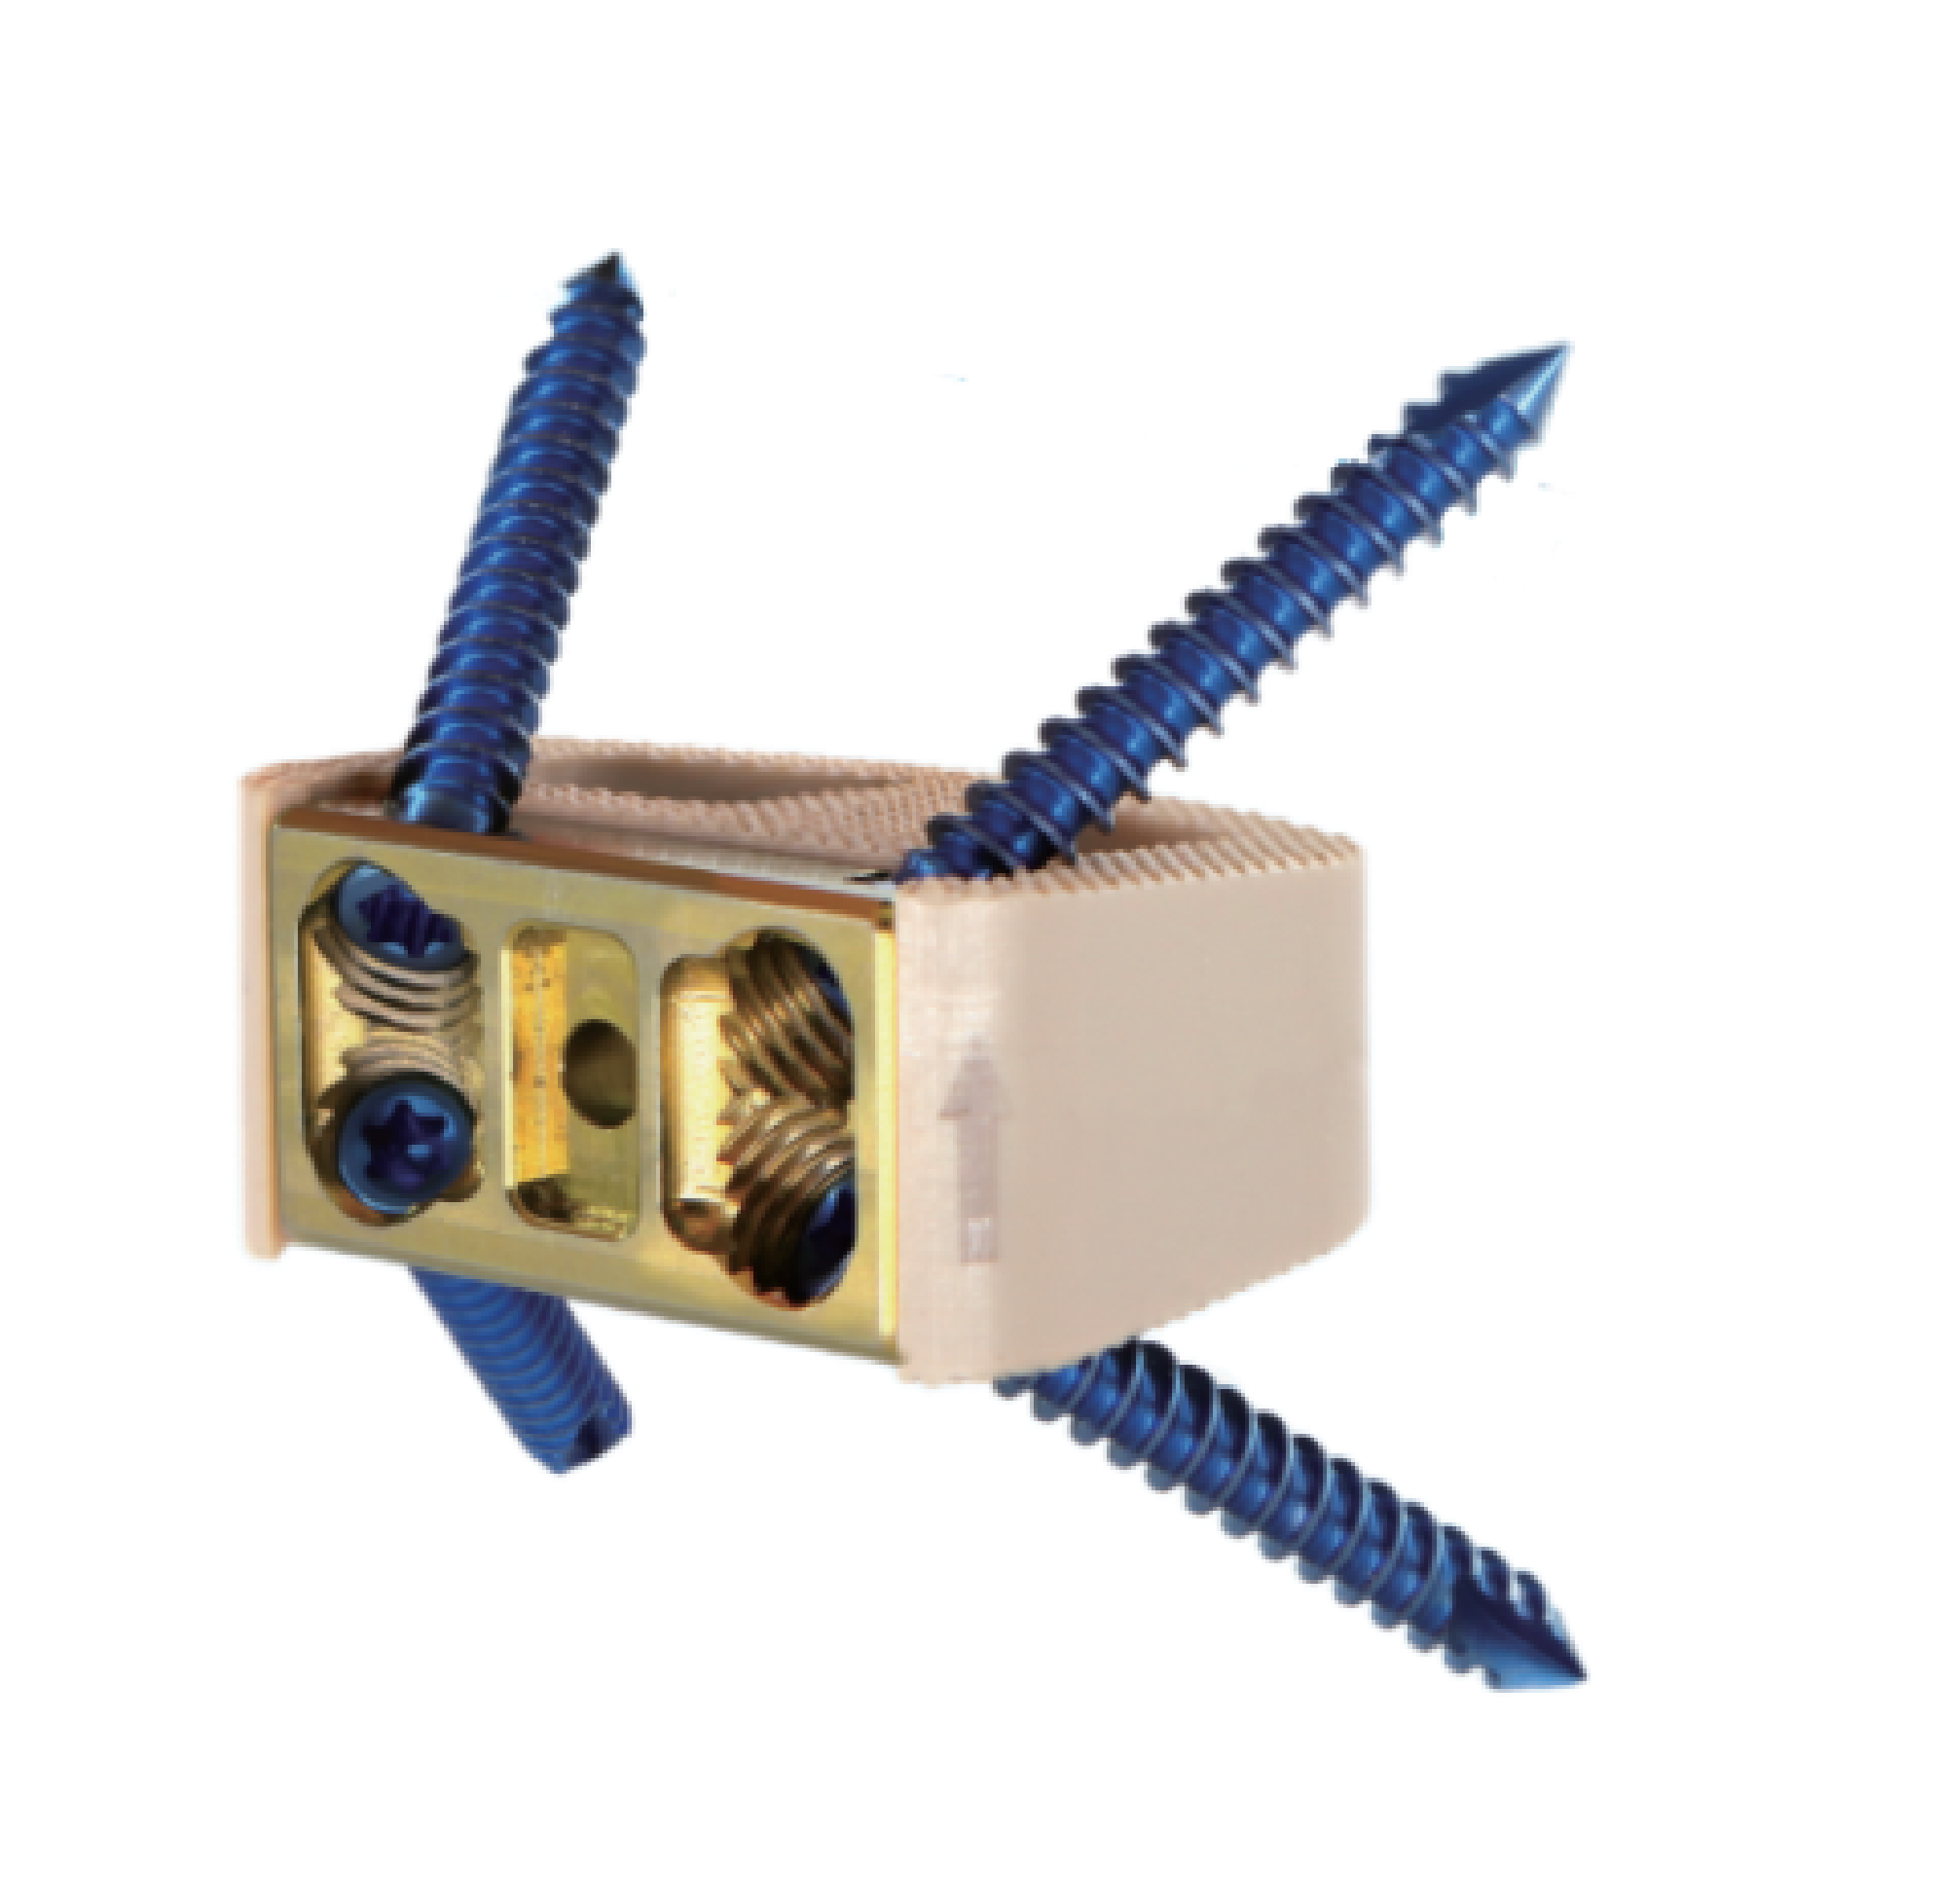

Self-Stabilizing Interbody Fusion Cage